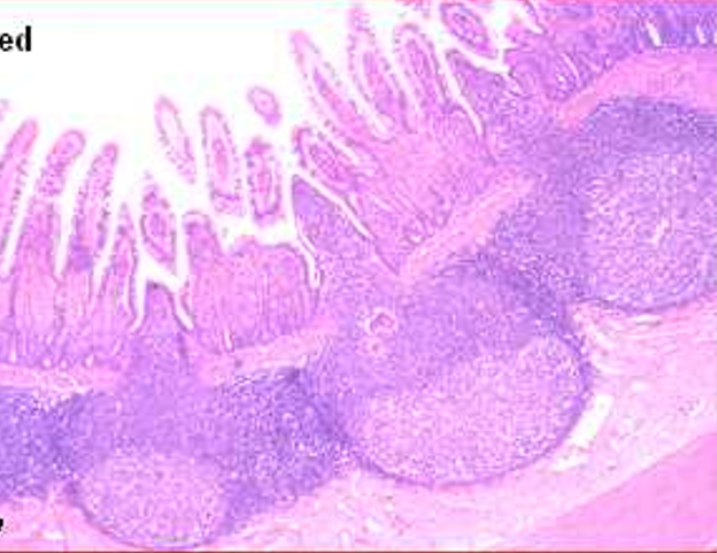

villi

this is from the

ileum

the arrow is pointed to a

Peyer’s patch